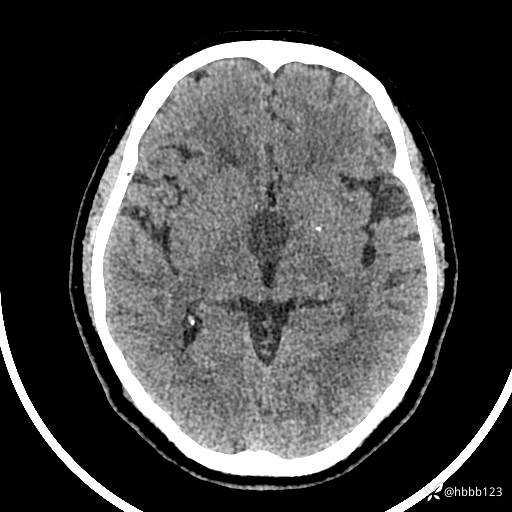

颅脑CT平扫: